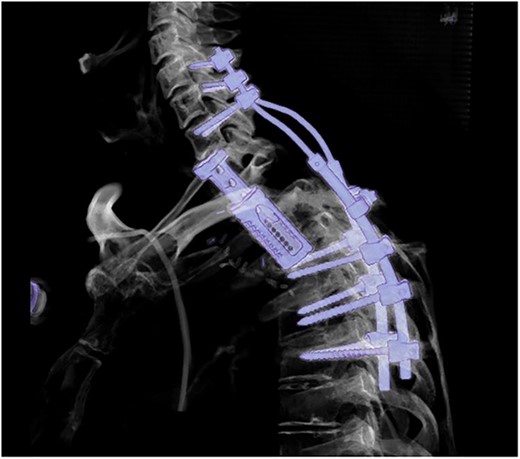

The surgical procedure was completed 5 days later without any complication by decompression of the exiting nerve roots of the first to third thoracic vertebra followed by consequently vertebral resection. After the placement of the distractable vertebral cage, the patient was shifted into the prone position. Then, the fifth cervical to the sixth thoracic vertebra was visualized and further dorsal tumor debulking with removal of the intraspinal mass was performed. Thereafter, lateral mass screws were inserted in C5 and C6. The vertebrae C7, Th4-6 were instrumented using pedicle screws. The rod system was implanted with additive cross-connector insertion (Figs 4 and 5). During the further postoperative course, skin and muscle tissue thinned out, leading to the transfer of a mucocutaneus latissimus dorsi flap over the screws by plastic surgeons 7 months later. Unfortunately, 1 year after the spine surgery, CT scans identified a local tumor recurrence involving C1 to Th6 with the infiltration of the spinal canal and chest wall in the CTJ. The patient suffered from pain in the right shoulder and a paresis of the right hand, which worsened to a mild paresis of the arm. Palliative chemotherapy with carboplatin and etoposide was initiated. The patient died 1 month later because of the further NSCLC progression.

Postoperative sagittal CT scans with 3D-reconstruction after 360° fusion. The vertebral body replacement with a distractable cage, which is displaced anteriorly because of a slight endplate sintering.